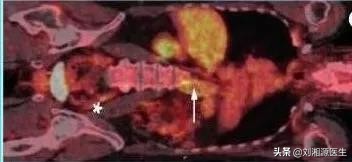

7)PET-CT:有助于大血管炎病情活动判断,见图8。

图8 大血管炎患者PET-CT显示降 主动脉和髂动脉有18F-FDG摄取